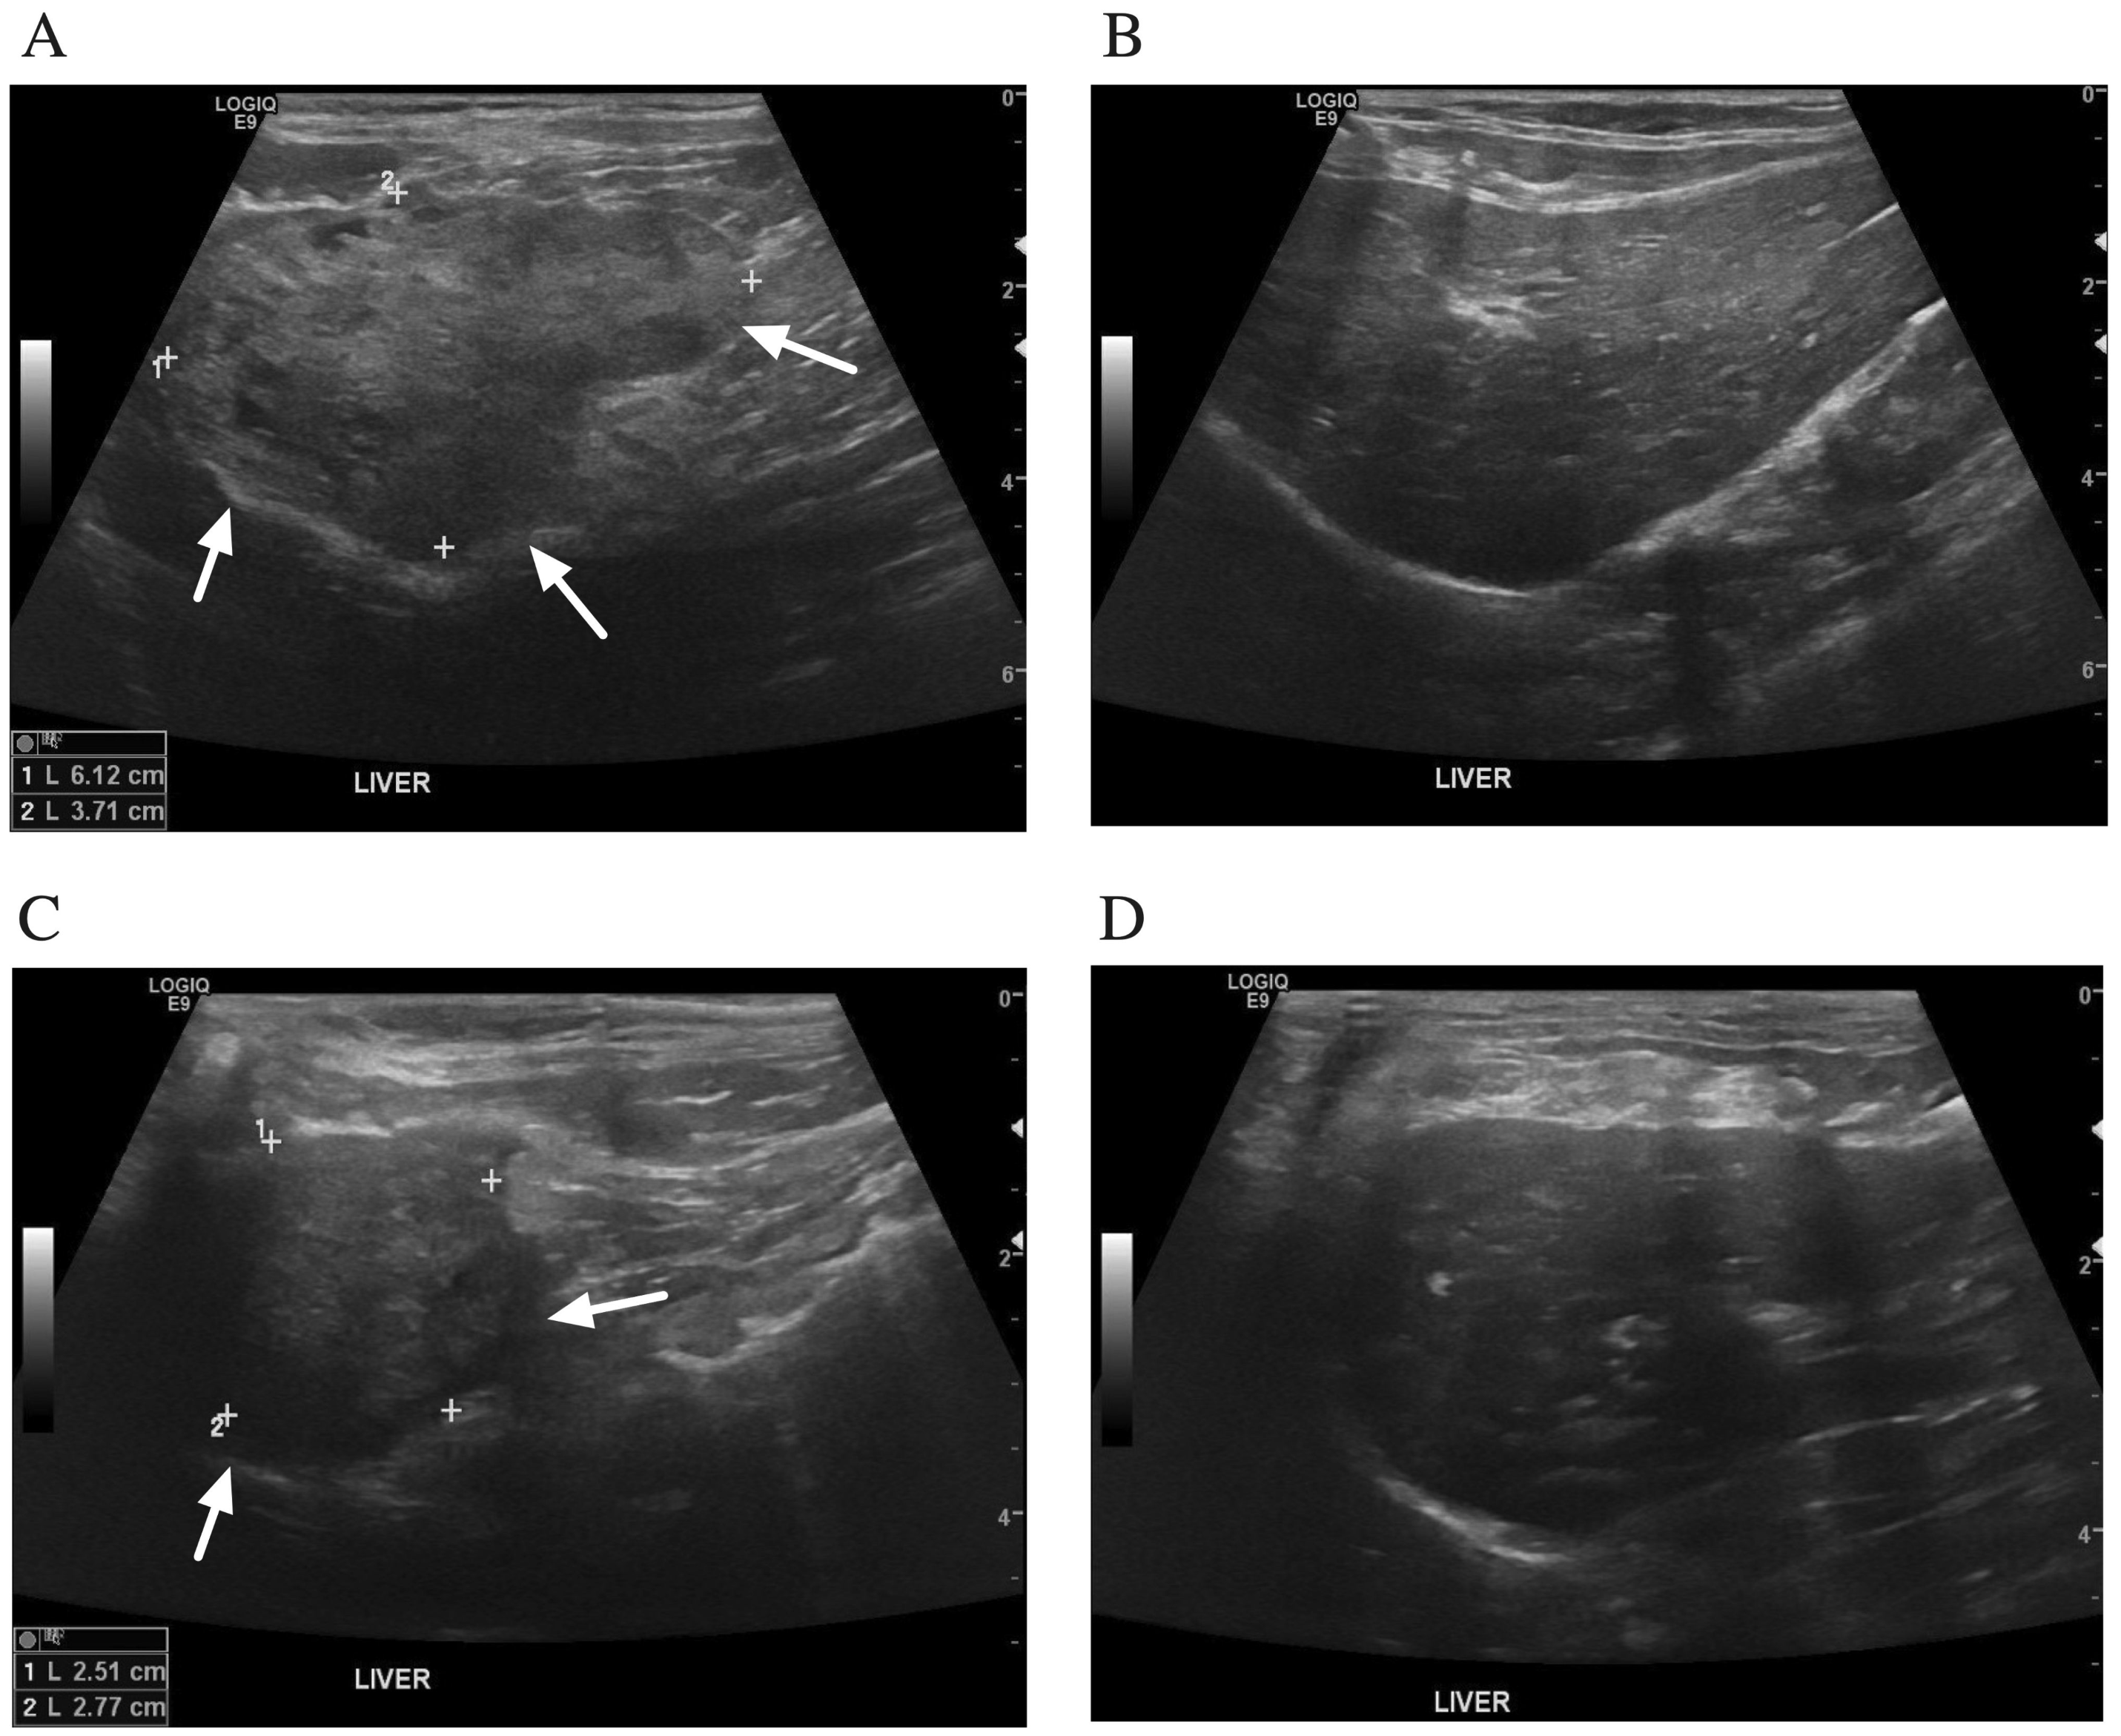

2. Case Description